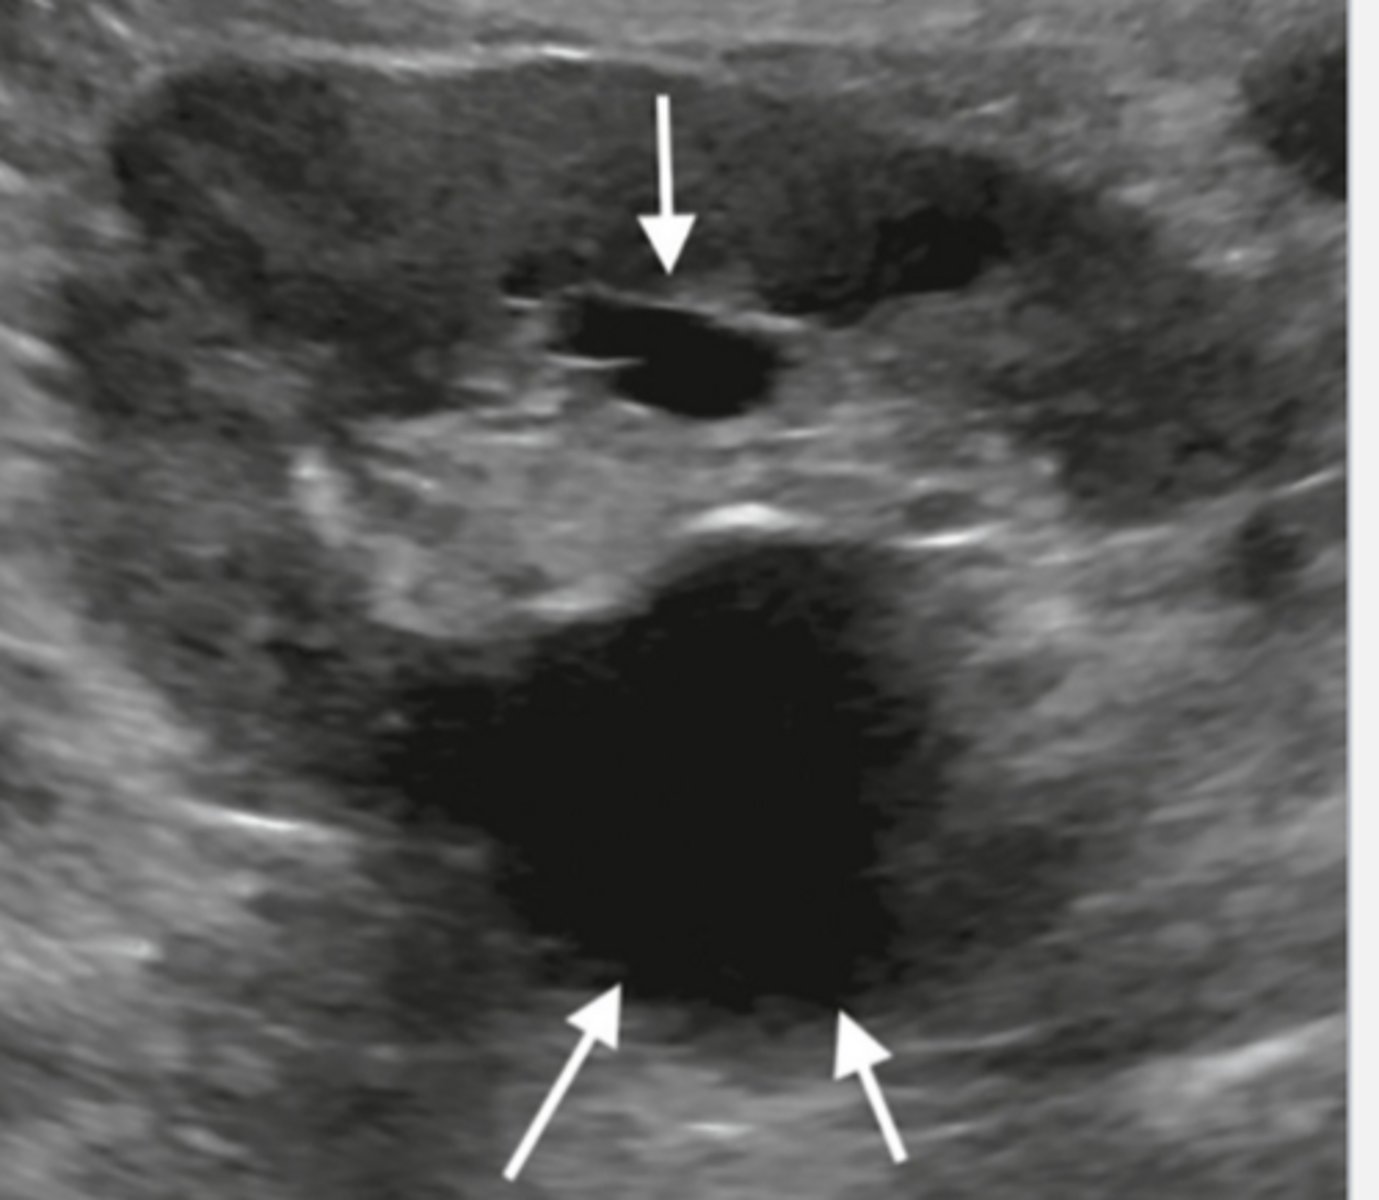

What grade of hydronephrosis is this?

Fluid extends into major and minor calyces. "Bear Claw" or

"Cauliflower" effect.

Grade 2